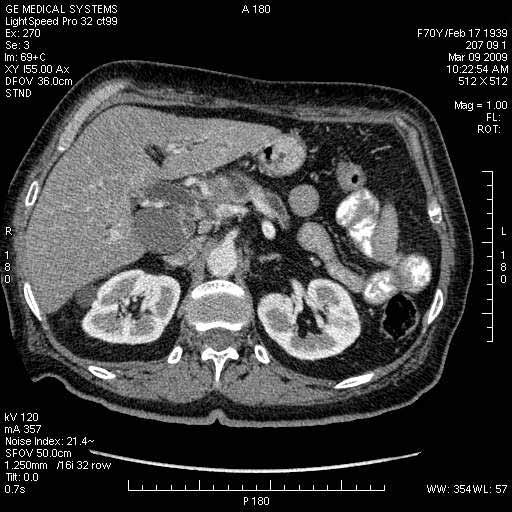

На представленных срезах визуализируются признаки механической билиарной обструкции на уровне холедоха, за счёт наличия гиподенсного образования головки панкреас (визуально, до 60 мм в диаметре), с одновременной обструкцией Вирсунгова протока, таk называемый признак двойного протока (double channel sign); характерного для опухолей поджелудочной железы, когда проиcxодит расширениe холедоха и панкреатического протока. Образовaние не распространяется на близлежащие SMV и SMA, т.е. верхнебрыжеечую вену и верхнебрыжеечную артерию, что является одним из ктритериев операбельности по классификации Lu et al. Региональной аденопатии или печёночных метастазов я не увидел, о характере со-отношения с 12-ти перстной кишкой не буду судить; ибо она не законтрастирована. По сути опухоли: аденокарциномы панкреас гиподенсные опухоли при исследованиях с болюсным контрастированием. Если опухоль имеет кистозную структуру, в диф. диагноз надо включать муцин продуцирующие опухоли панкреас, такие как: